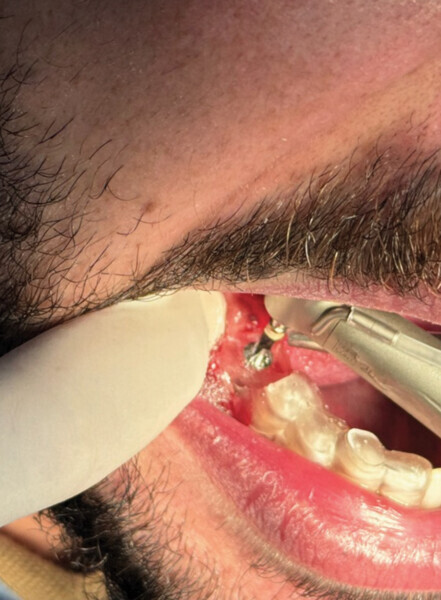

Fig. 1

Le patient, âgé de 27 ans, présentait un kyste apical ainsi qu’une atteinte de la furcation de la 46 ne nous permettant pas le retraitement et l’exérèse kystique. La décision de l’avulsion a donc été prise, en vue de la pose d’un implant (Fig. 1).

L’avulsion a été faite après anesthésie avec une ampoule de SEPANEST 40 mg adrénaline à 1/200000e. L’acte chirurgical est réalisé de manière la plus atraumatique possible, exérèse et curetage du kyste apical, nettoyage de l’alvéole. Dans ce cas précis, nous n’avons rien mis dans l’alvéole car les quatre murs alvéolaires ont pu être conservés. Un léger décollement des muqueuses vestibulaires et linguales a été nécessaire pour la mise en place de la membrane R.T.R.+.* La structure de cette membrane est faite pour être positionnée dans un sens précis, la surface lisse est toujours positionnée vers l’extérieur et la face rugueuse en regard de l’os.